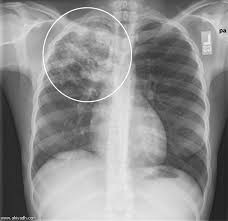

1– الدرن الرئوي .

http://www.madinahx.com/attachment.p...p;d=1332320234

كيف يمكن تشخيص الدرن الرئوى؟

1 – الفحص الإكلينكى .

2 – الفحص بالأشعة .

3 – الفحص المعملى لميكروب الدرن فى البصاق وعينات أخرى .